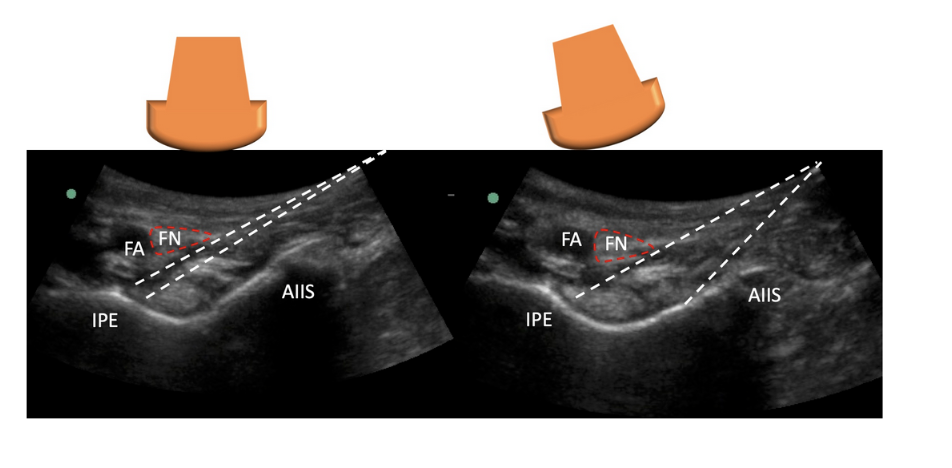

• Using a curvilinear probe, start inferior to the inguinal ligament to visualize the femoral head.

• The probe can be moved cranially until the AIIS and IPE is visualized.

• Once the “trench” or the “divot” is identified, then you need to visualize the important landmarks: femoral artery, nerve, vein, iliacus muscle, and psoas tendon

Identification of the AIIS, IPE, and femoral neurovascular bundle in the left hip